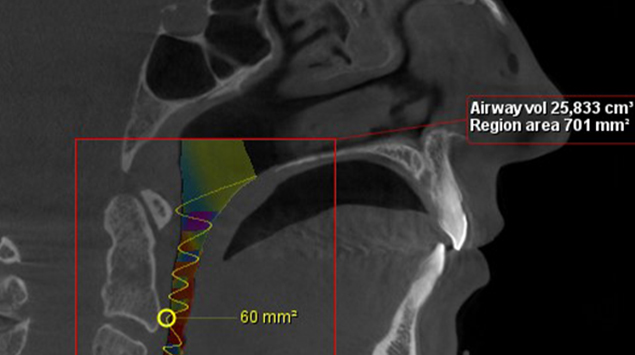

>   Zmiana w objętości dróg oddechowych po leczeniu ortodontyczno-chirurgicznym o ponad 70%